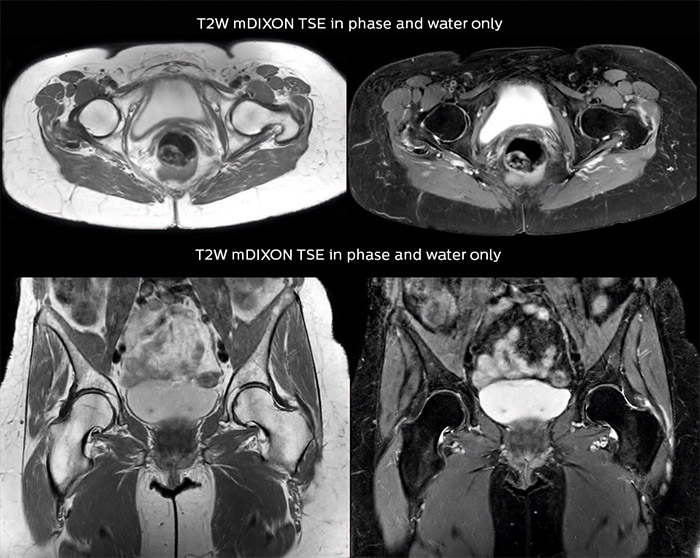

“For bone assessment near joints, mDIXON TSE provides the visualization and multiple contrasts to describe abnormalities within a limited number of acquisitions. Bone marrow signal abnormalities are common MRI findings that can represent various underlying causes, from normal variance to malignancy. So, it is important for us to notice and characterize these findings. With different contrasts, both with and without fat signal as mDIXON TSE efficiently provides, we can make a confident diagnosis.” “Other examples in bone are the signal description of a necrotic fragment in osteonecrosis, the signal description of tumoral matrix that has different components (necrosis, hemorrhage, cartilage, bone formation). These are all possible thanks to in-phase and water images from a single mDIXON acquisition.”

“In peripheral joints, mDIXON TSE imaging aids in diagnosing injuries in ligaments or tendons, for imaging degenerative and inflammatory pathologies such as osteoarthritis and rheumatologic disorders and for oncological exploration.” “For tendon and ligament assessment around knee, ankle, hip and elbow, mDIXON TSE contributes to diagnostic confidence thanks to having images both with and without fat suppression – and without time penalty. This is possible because 2-point mDIXON is faster than the common 3-point Dixon method. It can also increase efficiency as it helps avoid having to add scans during the exam.”

“In peripheral joints, we get good image quality in difficult areas with mDIXON TSE.

Fat suppressed images appear homogeneous over the entire image, even with large coverage at 3.0T – for instance in scapular or hip girdles – or in the bearing areas or around metal prostheses, where fat suppression is often deficient with STIR or spectral fat suppression, causing diagnostic difficulties. If a diagnostic image is right the first time, we don’t need to repeat or add a sequence.” “mDIXON TSE sequences allow simultaneous characterization of morphological changes from the in-phase T2-weighted images and visualization of edematous changes, thanks to the water T2-weighted images from the same acquisition. Anatomical and morphological considerations could be a partial or complete ligament tear, a bony avulsion or hematoma.” “For soft tissue assessment mDIXON brings similar benefits. For example in one T2-weighted mDIXON TSE acquisition, having the multiple contrasts helps us assess abnormalities in peripheral nerves fascicles, which may be due to anatomical or inflammatory changes..”